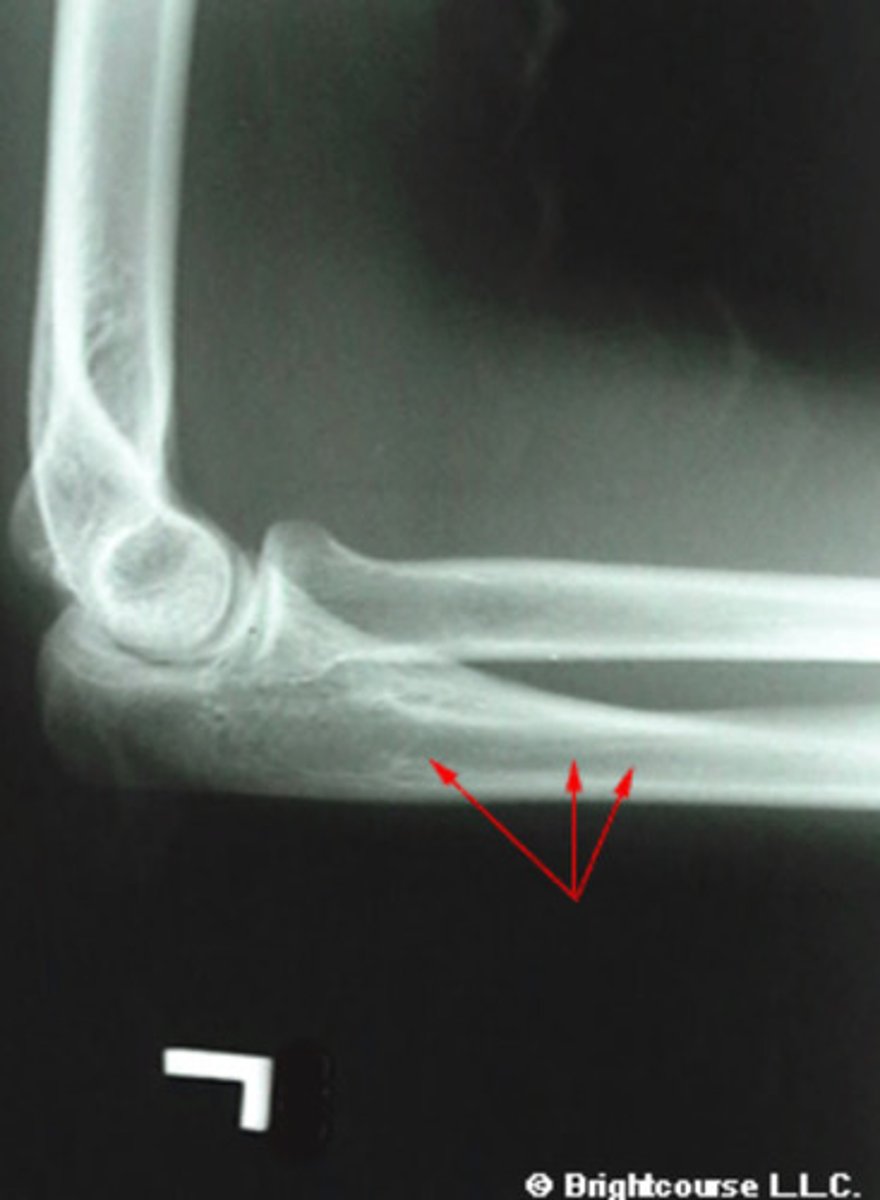

Olecranon process

What structure is being pointed out by the arrows?

Proximal shaft of ulnar